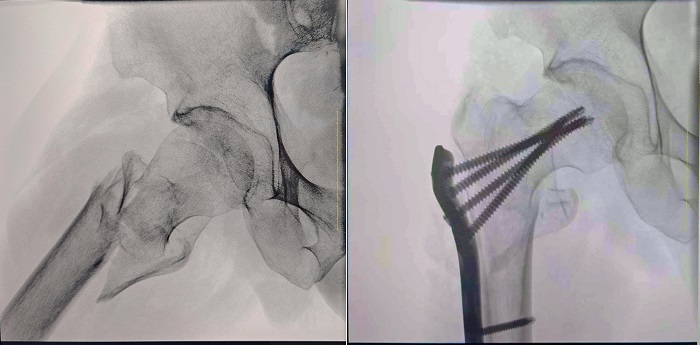

患者:70岁,男

临床诊断:右股骨粗隆间骨折,伴有下肢位移、外旋

术式:右股骨粗隆间骨折切开复位内固定术

一体式移动C型臂拍摄的术前影像

普爱医疗一体式移动C型臂采用30CM×30CM的平板探测器,能够帮助医生全面观察患者断端分离错位情况,确保手术方案的精准制定。